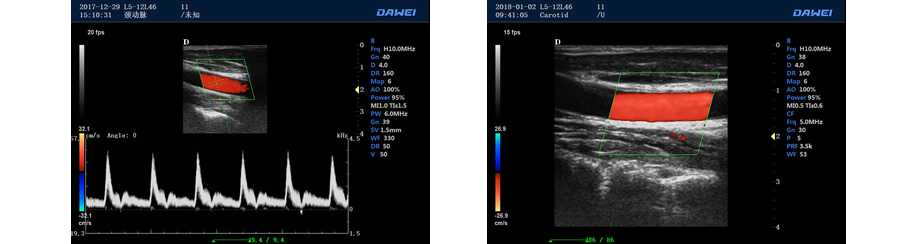

全數字彩色多普勒超聲診斷儀DW-PE522

DW-PF580

便攜式彩色多普勒

PIP智能畫中畫成像模式

實時三維成像單元 連續波多普勒成像單元

●彩色多普勒血流成像單元

多普勒模式

具有PW脈沖波多普勒和CW連續波多普勒

取樣容積大小,可視可調

采樣角度校正:-30-80度

脈沖重復頻率多段可調

實時自動多普勒包絡描述及自動測量與分析